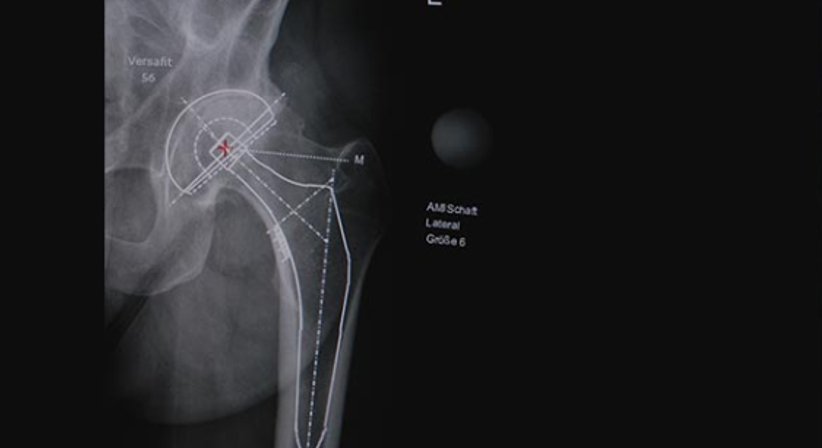

Jeder Operation geht eine digitale Planung voraus. Dabei werden die ideale Größe, Ausrichtung und Position der Hüftprothese bestimmt. Die Hüftendoprothese, die aus mehreren Komponenten besteht, ersetzt die Verbindung zwischen dem Oberschenkel- und Beckenknochen.

Ich operiere nach der minimal-invasiven, muskelschonenden (die Muskeln werden weder durchtrennt, noch abgelöst) AMIS Methode, die eine schnelle Heilung und rasche Genesung ermöglicht. Bei dieser Operationstechnik ist der Zugang zum Hüftgelenk von vorne. Dadurch kann das künstliche Hüftgelenk, die Hüftprothese, besonders behutsam eingesetzt werden. Die Prothese wird zementfrei implantiert, wobei der Knochen an die Implantatoberfläche aus Titan anwächst. Die Patienten können sich in der Regel einen Tag nach der Operation weitgehend schmerzfrei bewegen. Der Krankenhausaufenthalt dauert meist nicht länger als fünf bis sieben Tage.